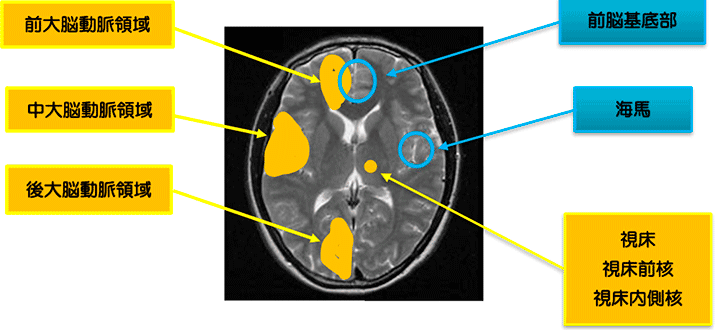

1. 大血管病変による血管性認知症

多発性大梗塞で、主幹動脈のアテローム血栓性脳梗塞や心原性脳塞栓症が含まれる。

2. Strategic single infarct dementia

視床前核、視床背内側核、海馬、前脳基底部などの、記憶に関与する重要な部分に生じた単一病変による認知症。

頻度は、血管性認知症の数%にとどまり、あまり高くはない。